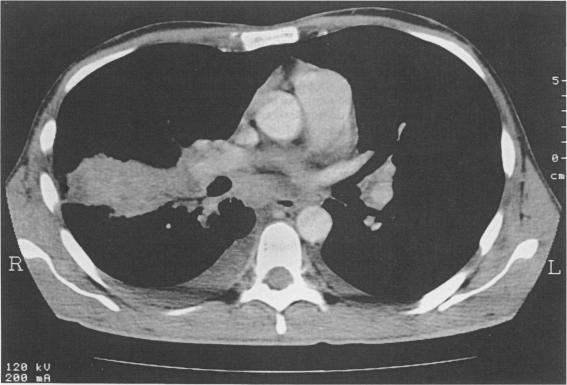

Individuals infected with the human immunodeficiency virus (HIV) are at an increased risk of both pulmonary and extrapulmonary tuberculosis. Disseminated cutaneous tuberculosis is rare, but has been reported in four HIV-positive patients, all of whom also had pulmonary infection. In this report we describe an HIV-infected patient with a febrile illness and an abnormal chest radiograph who developed widespread cutaneous tuberculous pustules following a lymph node biopsy on the previous day.

感染人类免疫缺陷病毒(HIV)的个体患肺结核和肺外结核的风险均会增加。播散性皮肤结核较为罕见,但已有4例HIV阳性患者的相关报道,所有这些患者同时也患有肺部感染。在本报告中,我们描述了一名感染HIV的患者,其患有发热性疾病且胸部X光片异常,在前一天进行淋巴结活检后出现了广泛的皮肤结核脓疱。